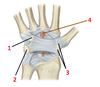

1? 2?

1: Acromio-clavicular ligament

2: Coraco-clavicular ligament